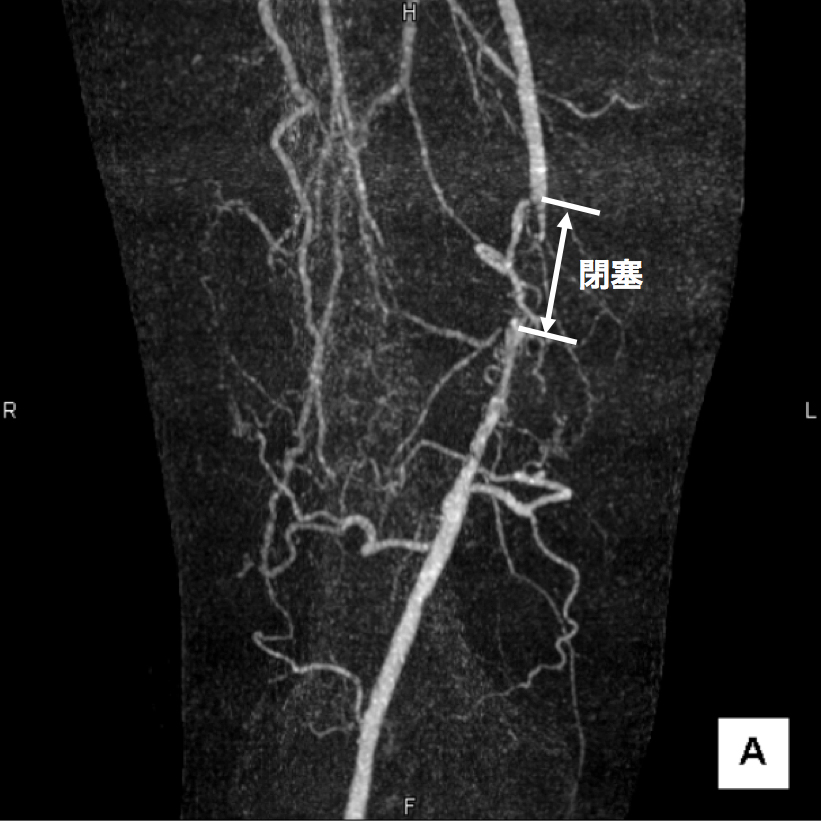

3、造影CT検査 造影剤を点滴しながらCTを撮像することで、血液の流れ、血管の状態などを把握します。情報量が多く治療方針を決定する場合に役立つので当院では特に力を入れている検査です。(図2、3、4)

図3

この画像は血管の立体的な走行の把握に有用です。

右足大腿部の血管に強い石灰化(動脈硬化の変化)があります。